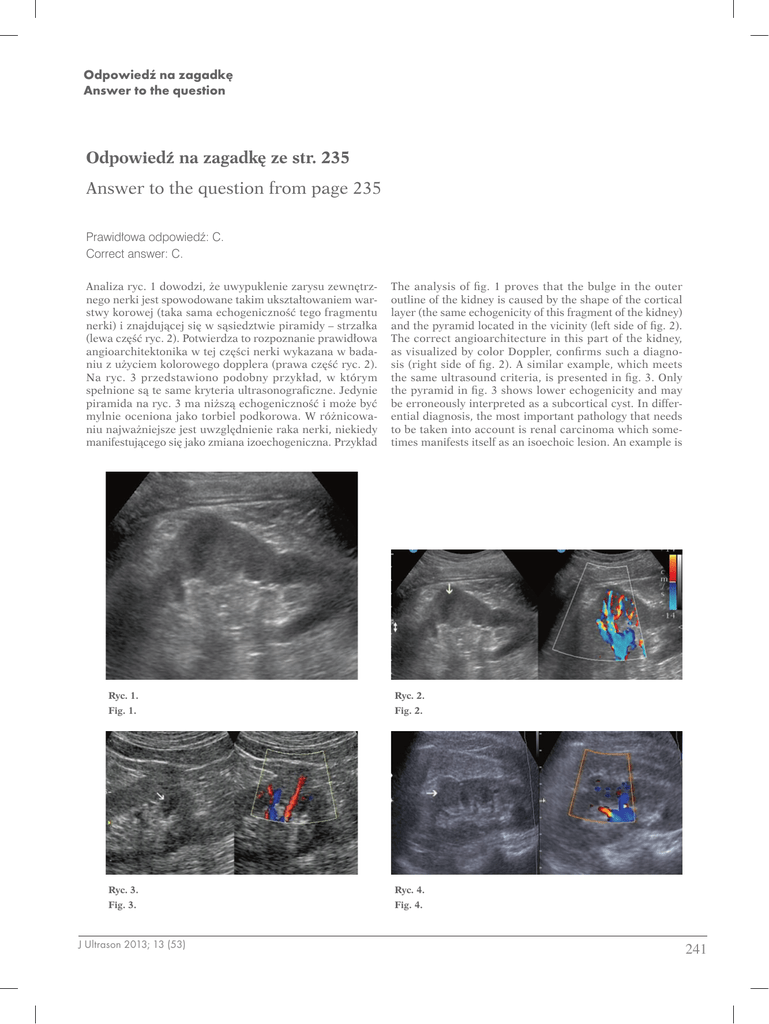

presented at the left side of fig. 4. The neoplasm reached

the size of 15 mm and practically, it is not different from

the surrounding parenchyma. The only alarming sign is

the chaotic central arrangement of the vessels in the nodule

(right side of the figure). Doubts may be resolved by scanning the same lesion with the patient assuming a standing position (fig. 5). In this figure, the lesion presented

in fig. 4 is better circumscribed, slightly hyperechoic and

with its appearance, it may imitate angiomyolipoma. However, when carefully observed, microcysts may be noticed,

which is a sign that does not normally accompany angiomyolipomas. It must be emphasized that the sonograms

in figs. 4 and 5 were obtained by the method of harmonic

imaging with pulse inversion. At this point, it is worth considering whether kidney examination should be performed